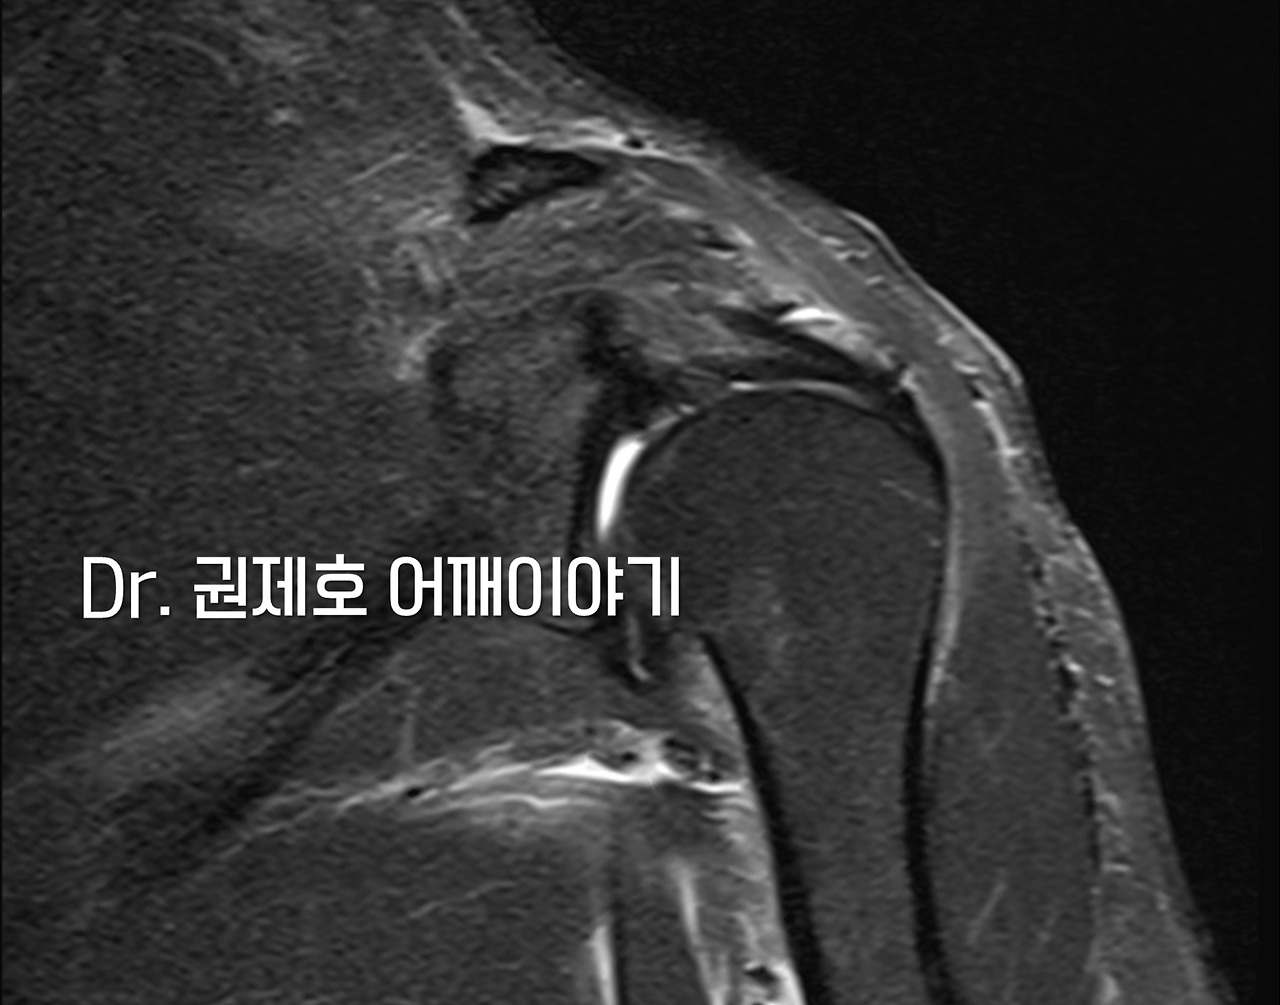

석회를 짜내는 과정에서 인대에 손상을 주진 않았을까 걱정하면서 다시 MRI검사를 했다. 이상은 없었다.